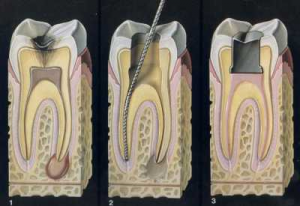

При лечении периодонтита используется методика, сходная с технологией лечения пульпита:

При лечении периодонтита используется методика, сходная с технологией лечения пульпита:

- Прежде всего, коронку зуба раскрывают, чтобы открыть доступ к корневым каналам.

- Затем под прикрытием антисептических препаратов из каналов начинают извлекать поражённые ткани. Эту манипуляцию производят аккуратно, дробно, постепенно продвигаясь к верхушке корня. Извлекая очередную порцию ткани, оборудование промывают в антисептике.

- В конце работы тщательно промывают весь канал и закладывают в него лекарственную пасту.

- Поверх пасты наносят временную пломбу.

- Через несколько дней в канал закладывают новую порцию пасты и вновь пломбируют зуб. Эту операцию производят до тех пор, пока воспалительный очаг окончательно не затихнет.